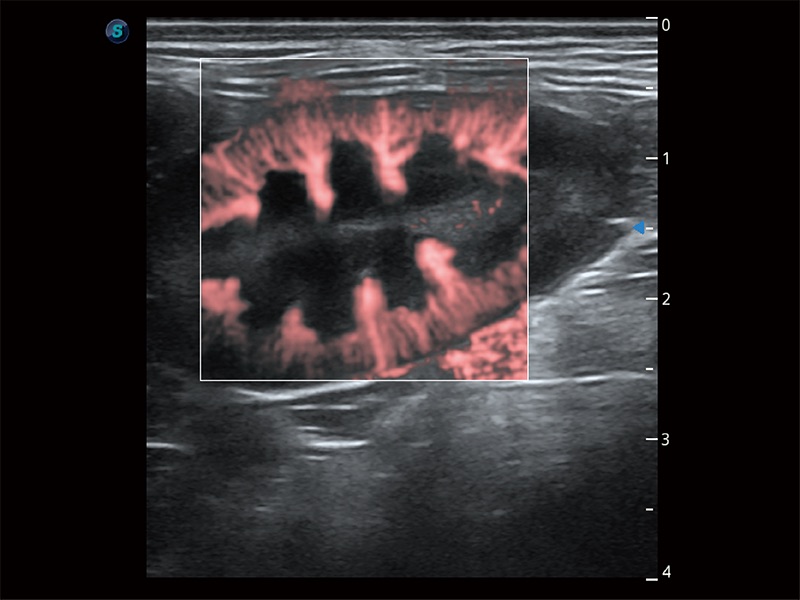

極大提升超低速微細(xì)血流的檢出能力,同時更精準(zhǔn)地濾除軟組織和超聲信號,為獸用醫(yī)生提供以往無法通過常規(guī)血流獲得的疾病診斷信息。

在傳統(tǒng)二維血流成像的基礎(chǔ)上,呈現(xiàn)血流的立體感,具有動感的生命力之美。即便是微小的血管也能輕松應(yīng)對,提高了血流的視覺敏感性。